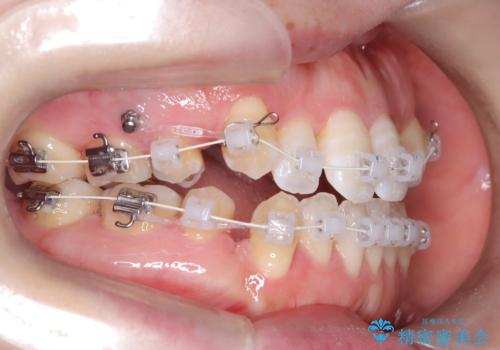

- 前歯のガタガタや八重歯の位置の乱れが気になっていた患者様に対して、ワイヤー矯正を行いました。矯正の過程で、スペースを確保するために上下左右の小臼歯を抜歯し、歯全体のバランスと機能性を考慮しながら理想的な歯列に仕上げました。

抜歯によって確保したスペースを活用し、効率的に歯列を整えました。前歯のガタガタと八重歯が解消され、自然で美しい仕上がりを実現しました。